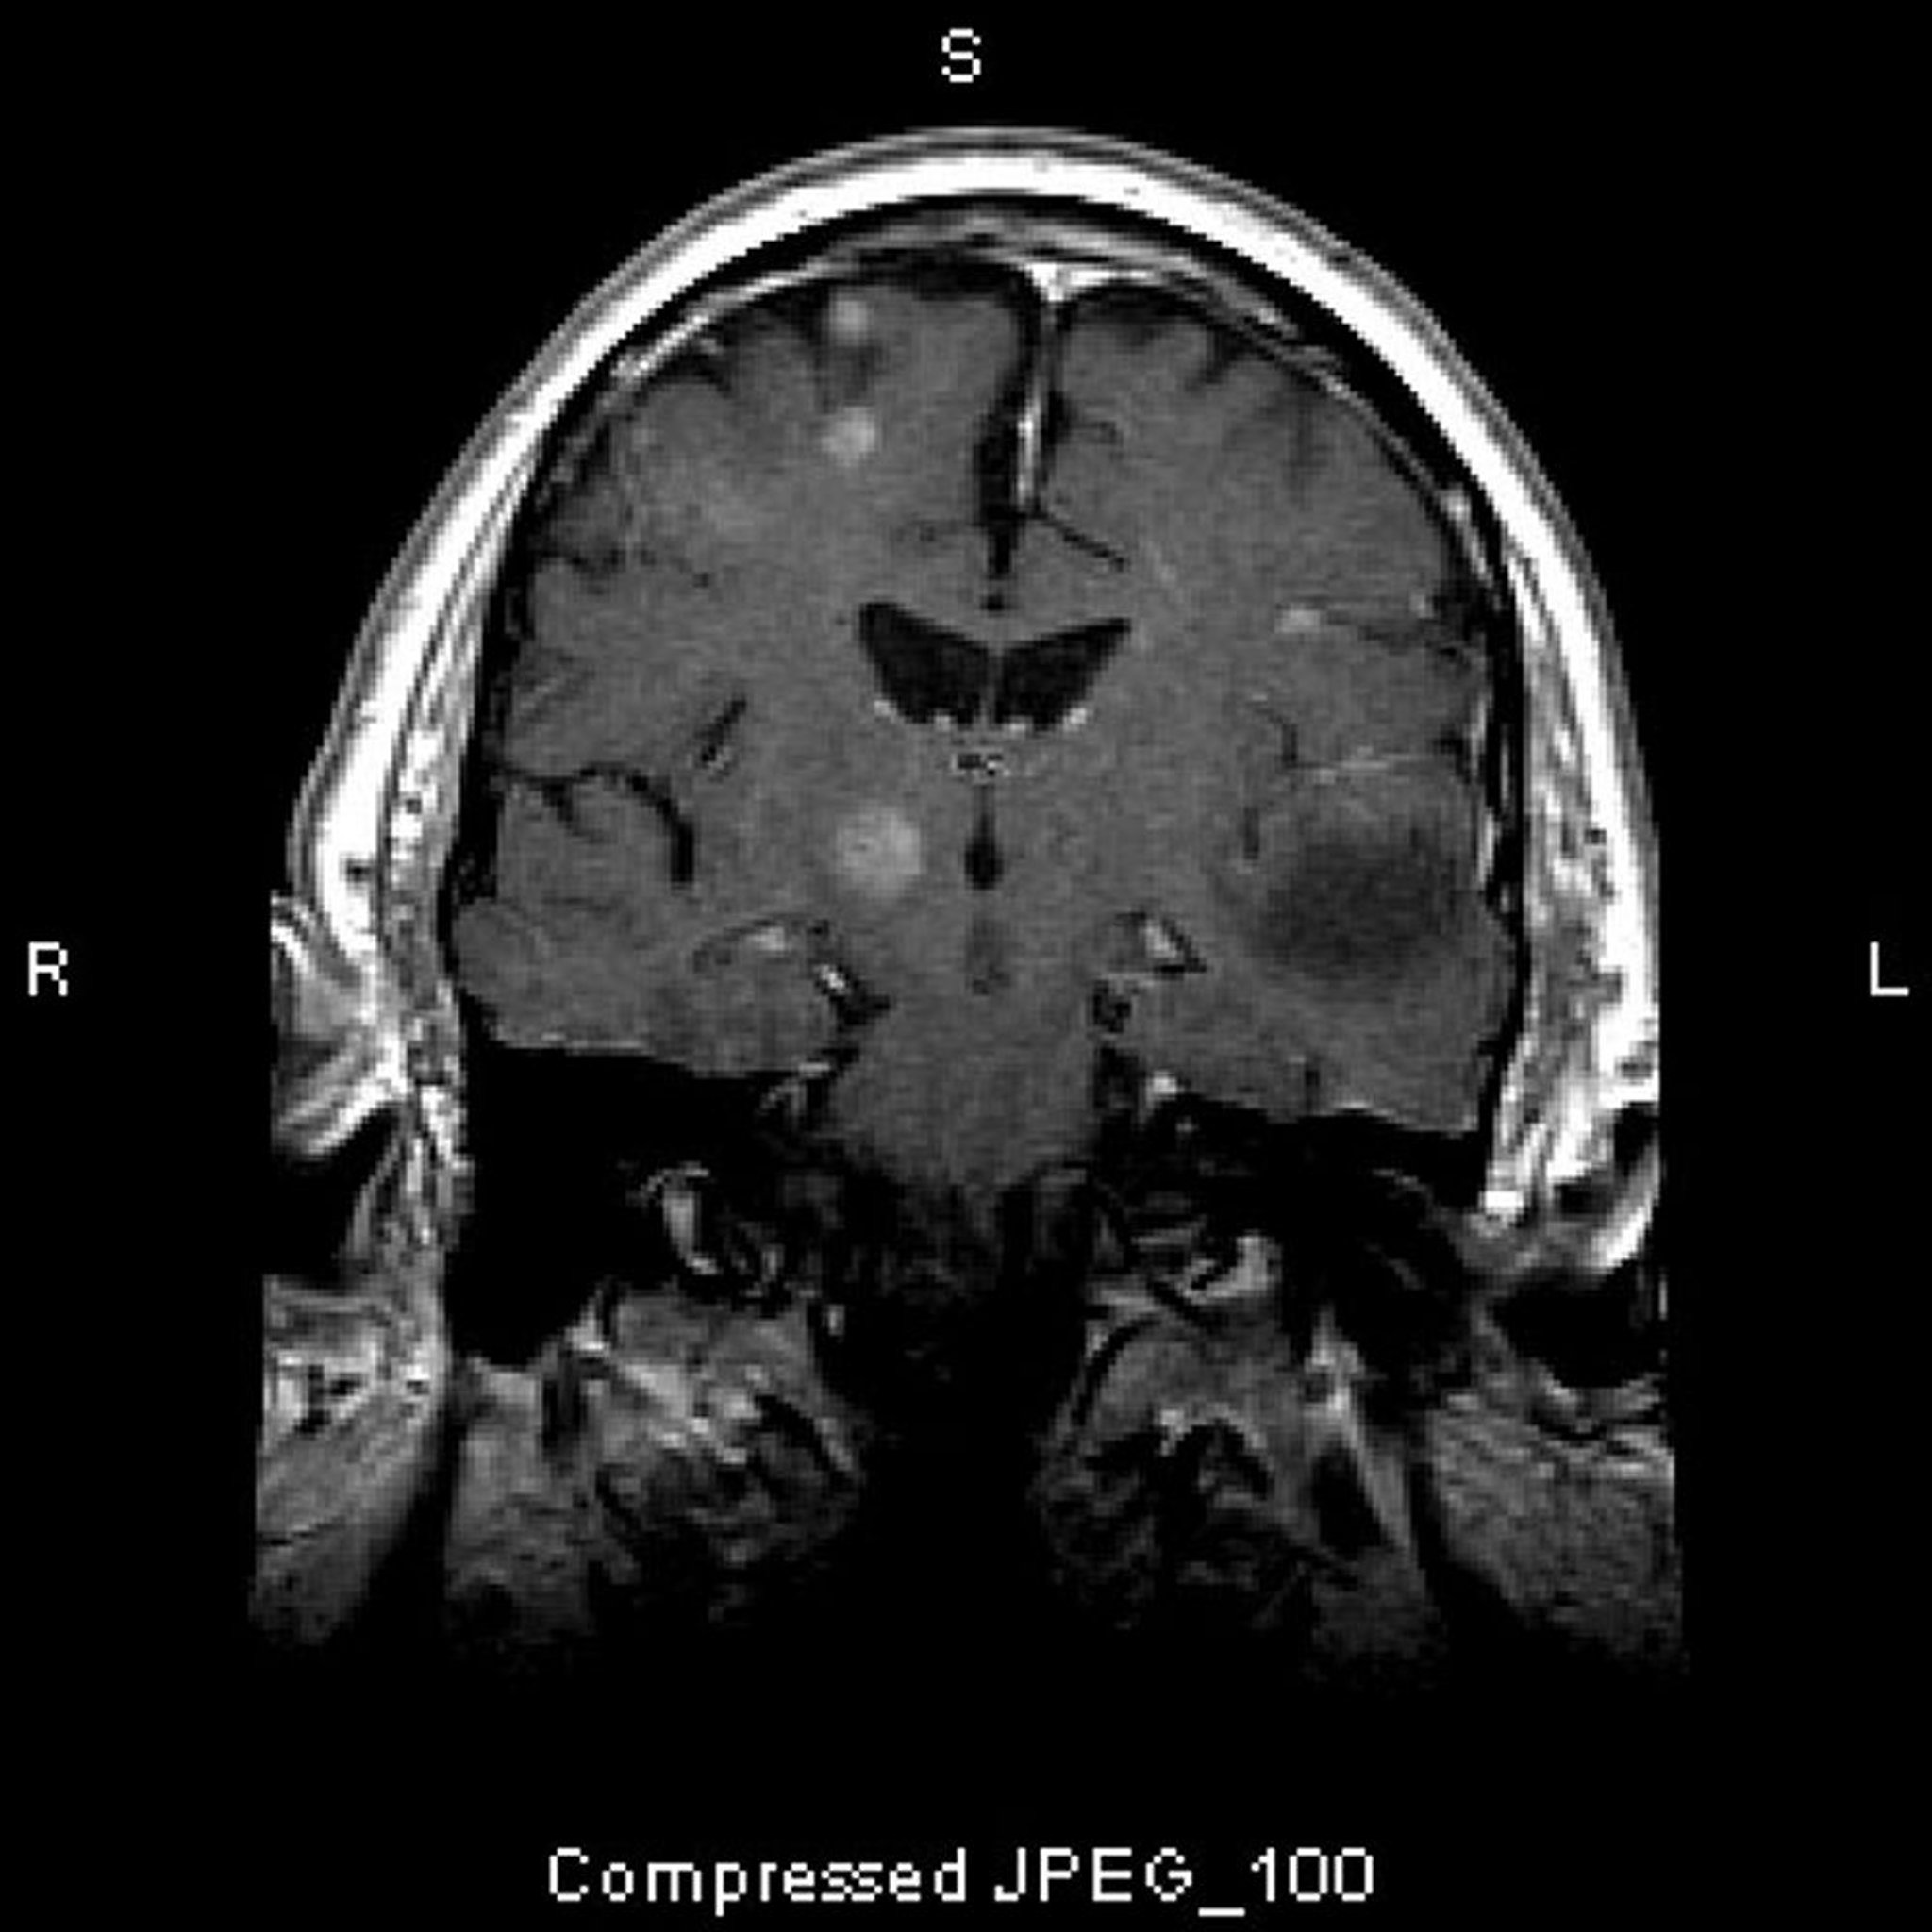

Метастазы в головной мозг

Этот снимок МРТ показывает множественные поражения головного мозга, представляющие собой метастатические опухоли. Более 80% метастазов в мозг – множественные.

Image courtesy of William R. Shapiro, MD.